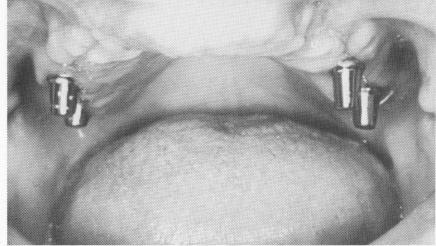

Fig. 11-183. Healing after 2 weeks.